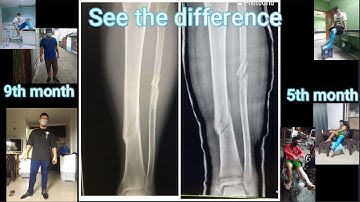

un video de tibia